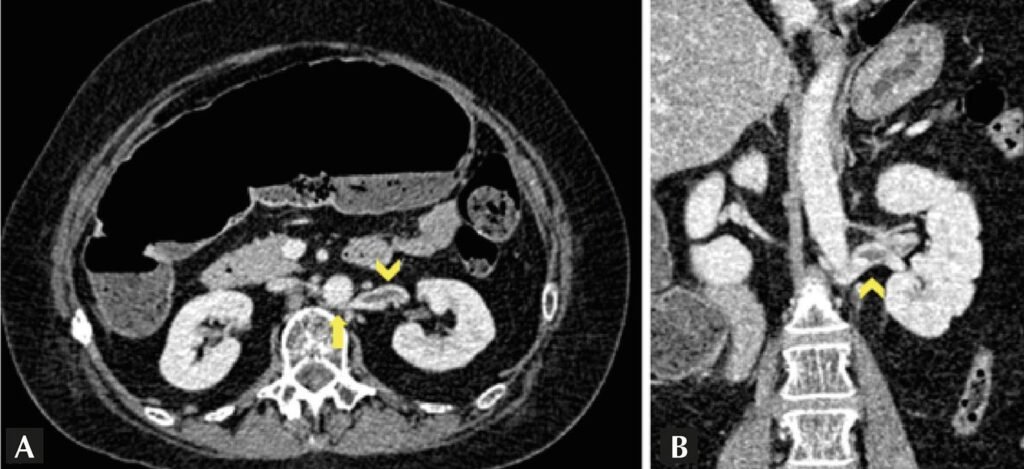

Paciente do sexo feminino, 56 anos, deu entrada no pronto atendimento com quadro de abdome agudo obstrutivo. Negava comorbidades ou cirurgias prévias. Foi submetida à tomografia de abdome que evidenciou volvo de ceco e achado incidental de trombose crônica recanalizada de veia renal esquerda com trajetória retroaórtica (fenômeno de “quebra-nozes” posterior). Foi submetida à laparotomia exploradora com colectomia direita e ileo transverso anastomose. Após evolução gradual da dieta, recebeu alta hospitalar no décimo dia de pós-operatório. No seguimento ambulatorial, negava sintomas de dor abdominal ou em flanco, e os exames laboratoriais não demonstraram indícios de proteinúria ou hematúria. Tendo em vista paciente com achado incidental de fenômeno de quebra-nozes, foi optado por tratamento conservador e seguimento periódico.

A veia renal esquerda retroaórtica é uma variação anatômica rara e, na maioria dos casos, assintomática, sendo denominada de “fenômeno de quebra-nozes posterior”. Quando apresenta sintomas, utiliza-se o termo “síndrome do quebra-nozes posterior”., A prevalência exata é desconhecida, porém, sabe-se que essa afecção é mais comum em pacientes do sexo feminino entre a terceira e quarta décadas. O quadro compressivo pode resultar em hipertensão venosa com dilatação da veia renal, varizes ureterais e de pelve renal, manifestando-se como hematúria macro e microscópica, dor no flanco e proteinúria., O tratamento conservador é empregado para pacientes assintomáticos ou oligossintomáticos, como descrito nesse caso.